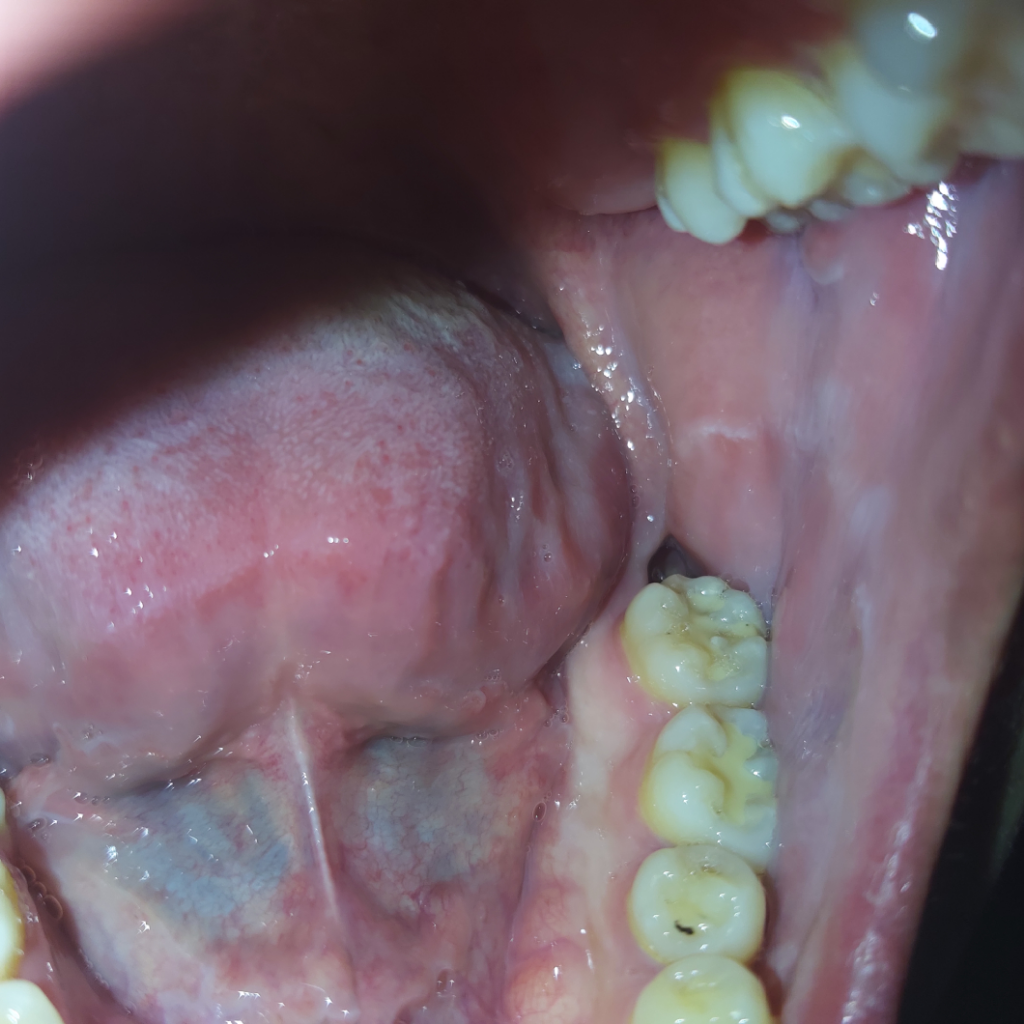

아래 매복 사랑니 발치 2주가 되었는데 발치부위 색이 이렇게 붉은지?

매복사랑니를 발치 후 약 2주가 되가는데 아직까지도 발치 부위가 불그스름해 질문드립니다. 잘 치유되고 있는 것 맞겠죠...?!

사진상으로는 염증같은 특별한 이상이 보이지 않습니다. 잘 낫고 있는 것으로 판단됩니다.

사진으로만 봤을 경우에는 발치와에 형성된 혈병이 제거된 상태로 보입니다.

잇몸이 아무는데는 2주정도의 시간이 걸리지만 해당부위를 자주 자극하게 되면 시간이 더 걸릴수도 있습니다.

2주 지난 상태이면 정상적으로 아물고 있는 것입니다. 어느정도 다 아무는데는 몇개월이 걸립니다. 아직까지는 건드리면 피가 나고 아플 수도 있지만 별다른 문제 되지 않습니다.

2주정도면 아직은 상처가 잇을 시기입니다. 상처는 최소 한달이상은 지나야 괜찮아 지실꺼에요.